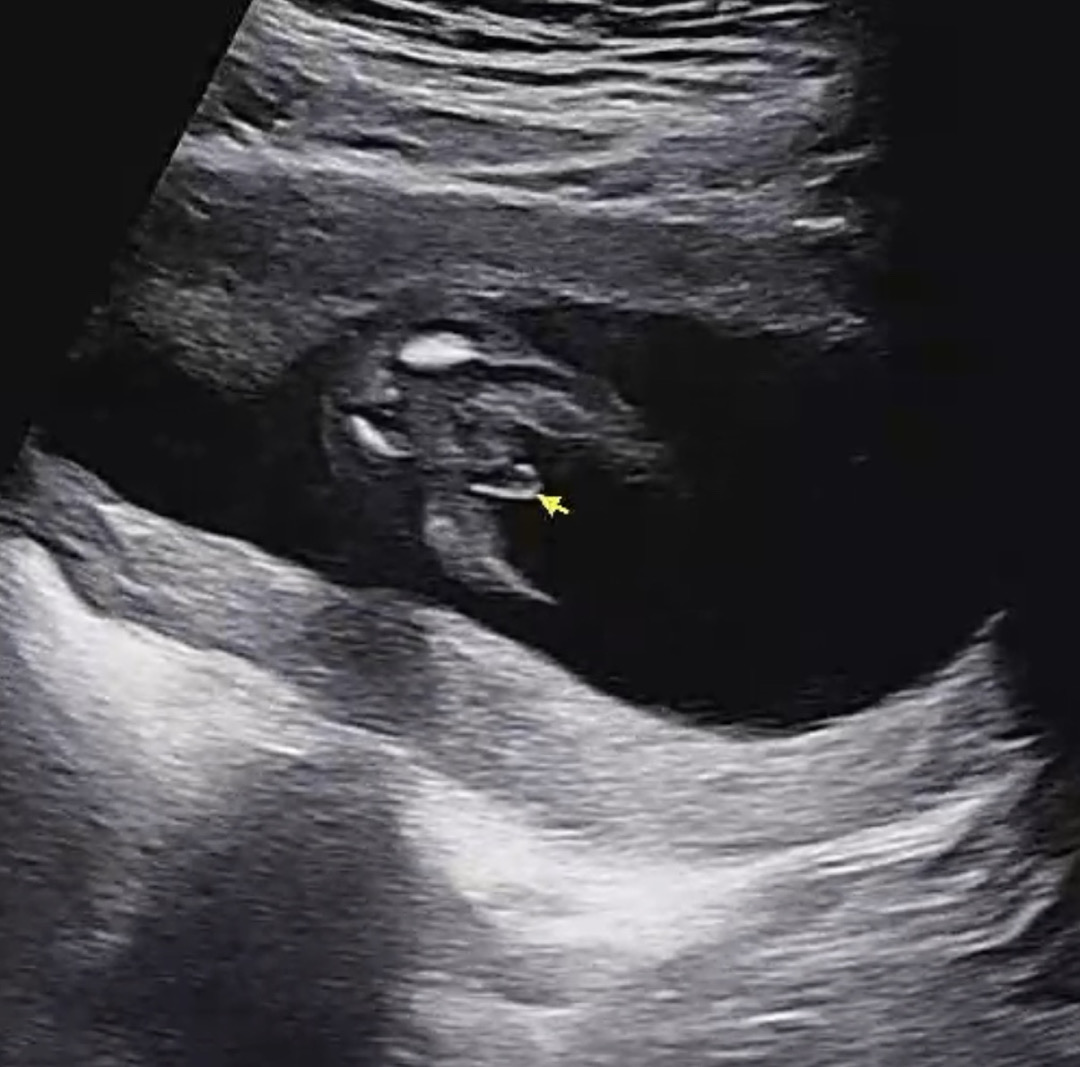

아들이 맞을까요…?

선생님이 웃으시며 뭐가보인다고하시는데… 탯줄일수도있나요!!?? 딸일수도있나요!?

너무 뚜렷한것같아요ㅎㅎ 몇주차에 보셨나요? 20주차에 바뀌시는분들도 꽤있더라구용